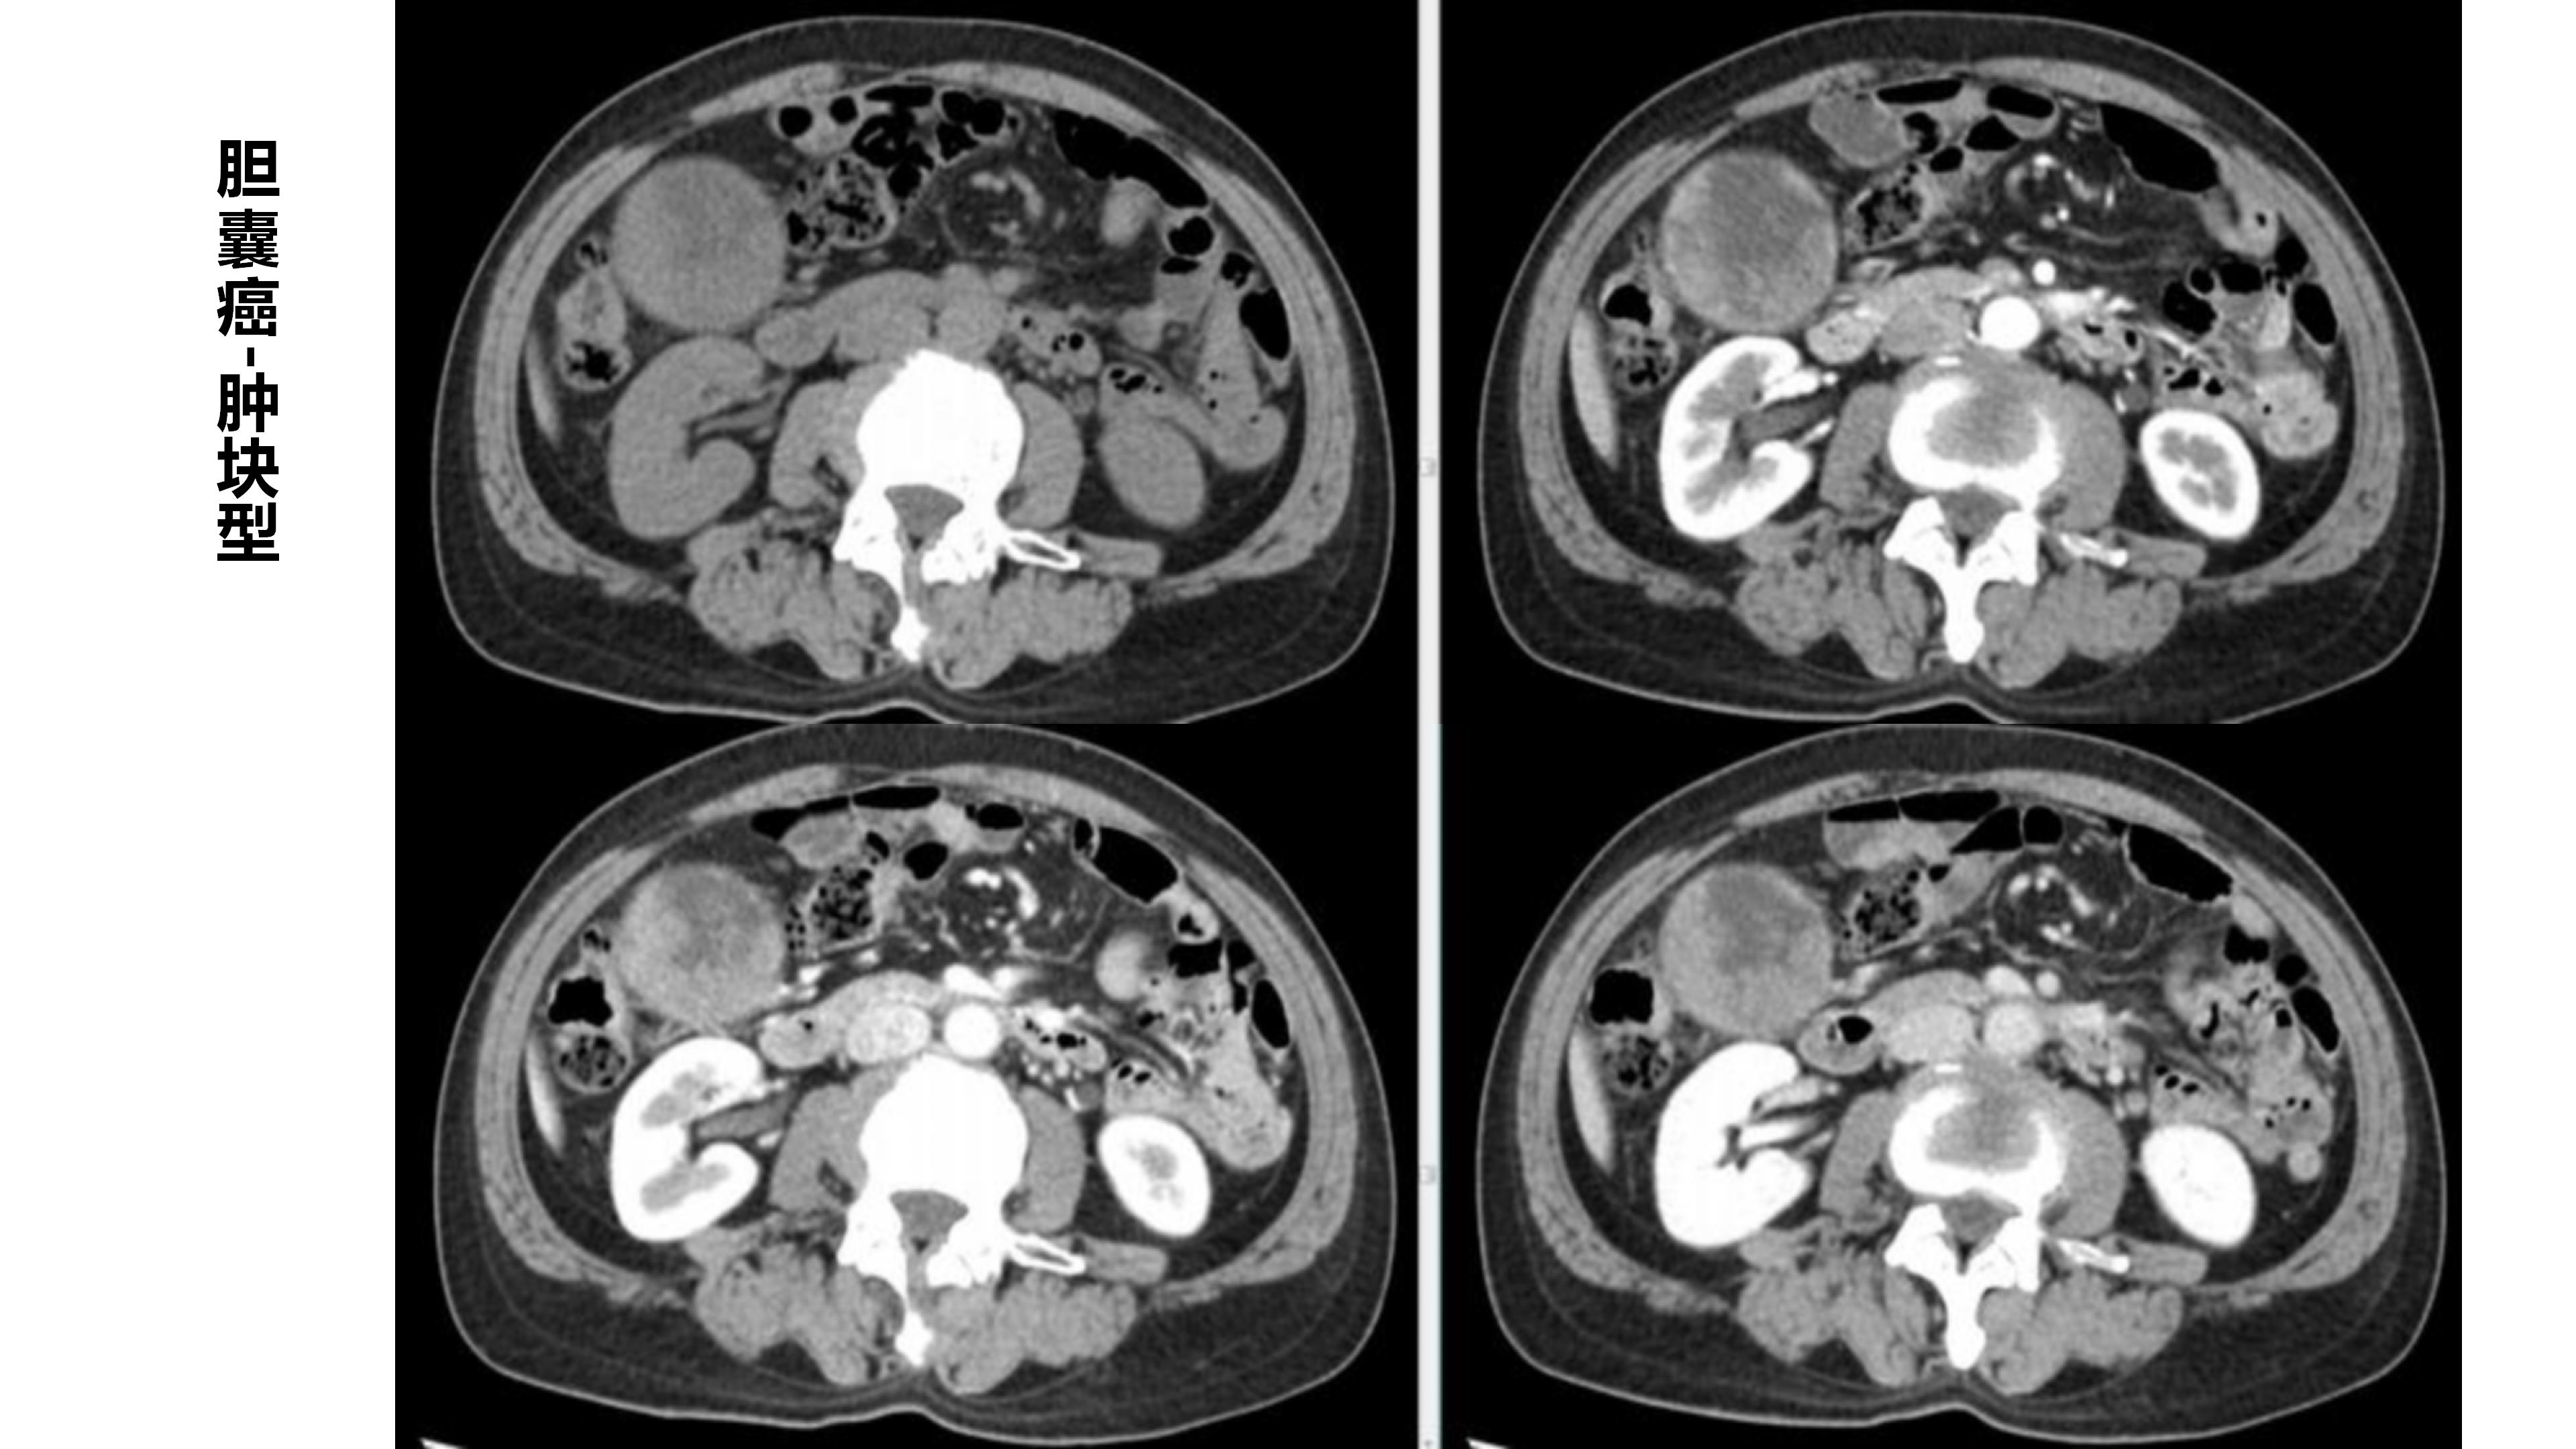

胆囊癌-鼎湖社群读片病例